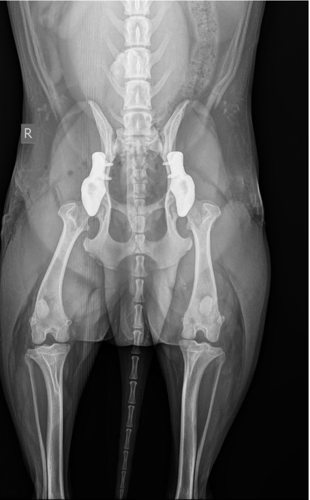

« Dans un premier temps, nous avons opté pour un traitement avec des analgésiques et du repos, car les prothèses 3D n’étaient pas encore disponibles en Belgique à l’époque », précise Tom Volkaert. « Mauro était éligible à une approche innovante avec des prothèses de hanche entièrement personnalisées et imprimées en titane 3D. » Sur la base d’un scanner CT, un implant a été conçu à l’aide d’un logiciel CAO, puis imprimé en titane couche par couche. L’implant stabilise les hanches afin d’empêcher toute luxation ultérieure. Grâce à une technique chirurgicale peu invasive, Mauro a pu marcher immédiatement après l’opération et a été autorisé à rentrer chez lui dans les 24 heures.

L’opération a été réalisée avec succès chez AniCura Dierenartsencentrum Herckenrode, en collaboration avec le Dr Marc Vanhoegaerden de AniCura Dierenkliniek Den Eikbos. « Cela montre que l’innovation et la collaboration au sein d’équipes spécialisées peuvent réellement faire la différence pour le bien‑être et la santé des animaux de compagnie », souligne Tom Volkaert. Cette intervention est désormais proposée dans les deux cliniques depuis janvier.

Le maître de Mauro se déclare également très satisfait. Mauro est aujourd’hui complètement rétabli : il se déplace sans douleur, marche et joue normalement, et a pleinement retrouvé sa mobilité.